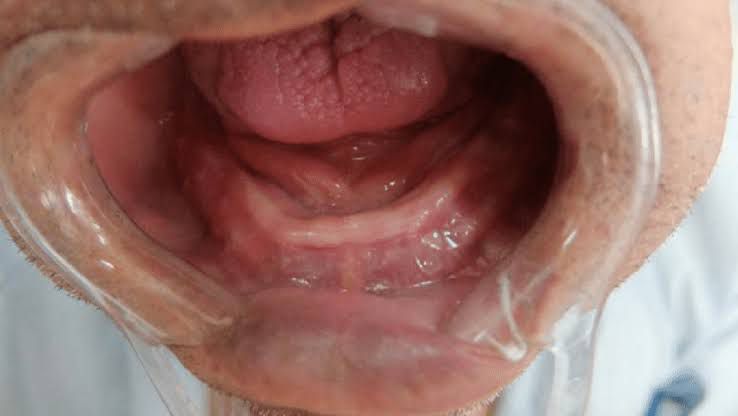

Residual alveolar ridge

“Residual alveolar ridge is that portion of the alveolar ridge and its soft tissue covering which remains following the removal or loss of teeth”.